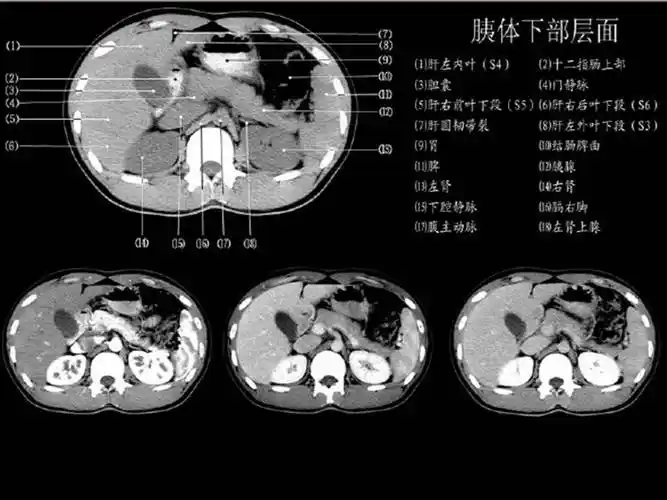

超赞!最全肝脏的表面解剖及分叶分段

couinaud肝脏分段系统ct图谱

结合解剖看腹部ct,轻松掌握肝脏读片!_静脉_水平_脏器